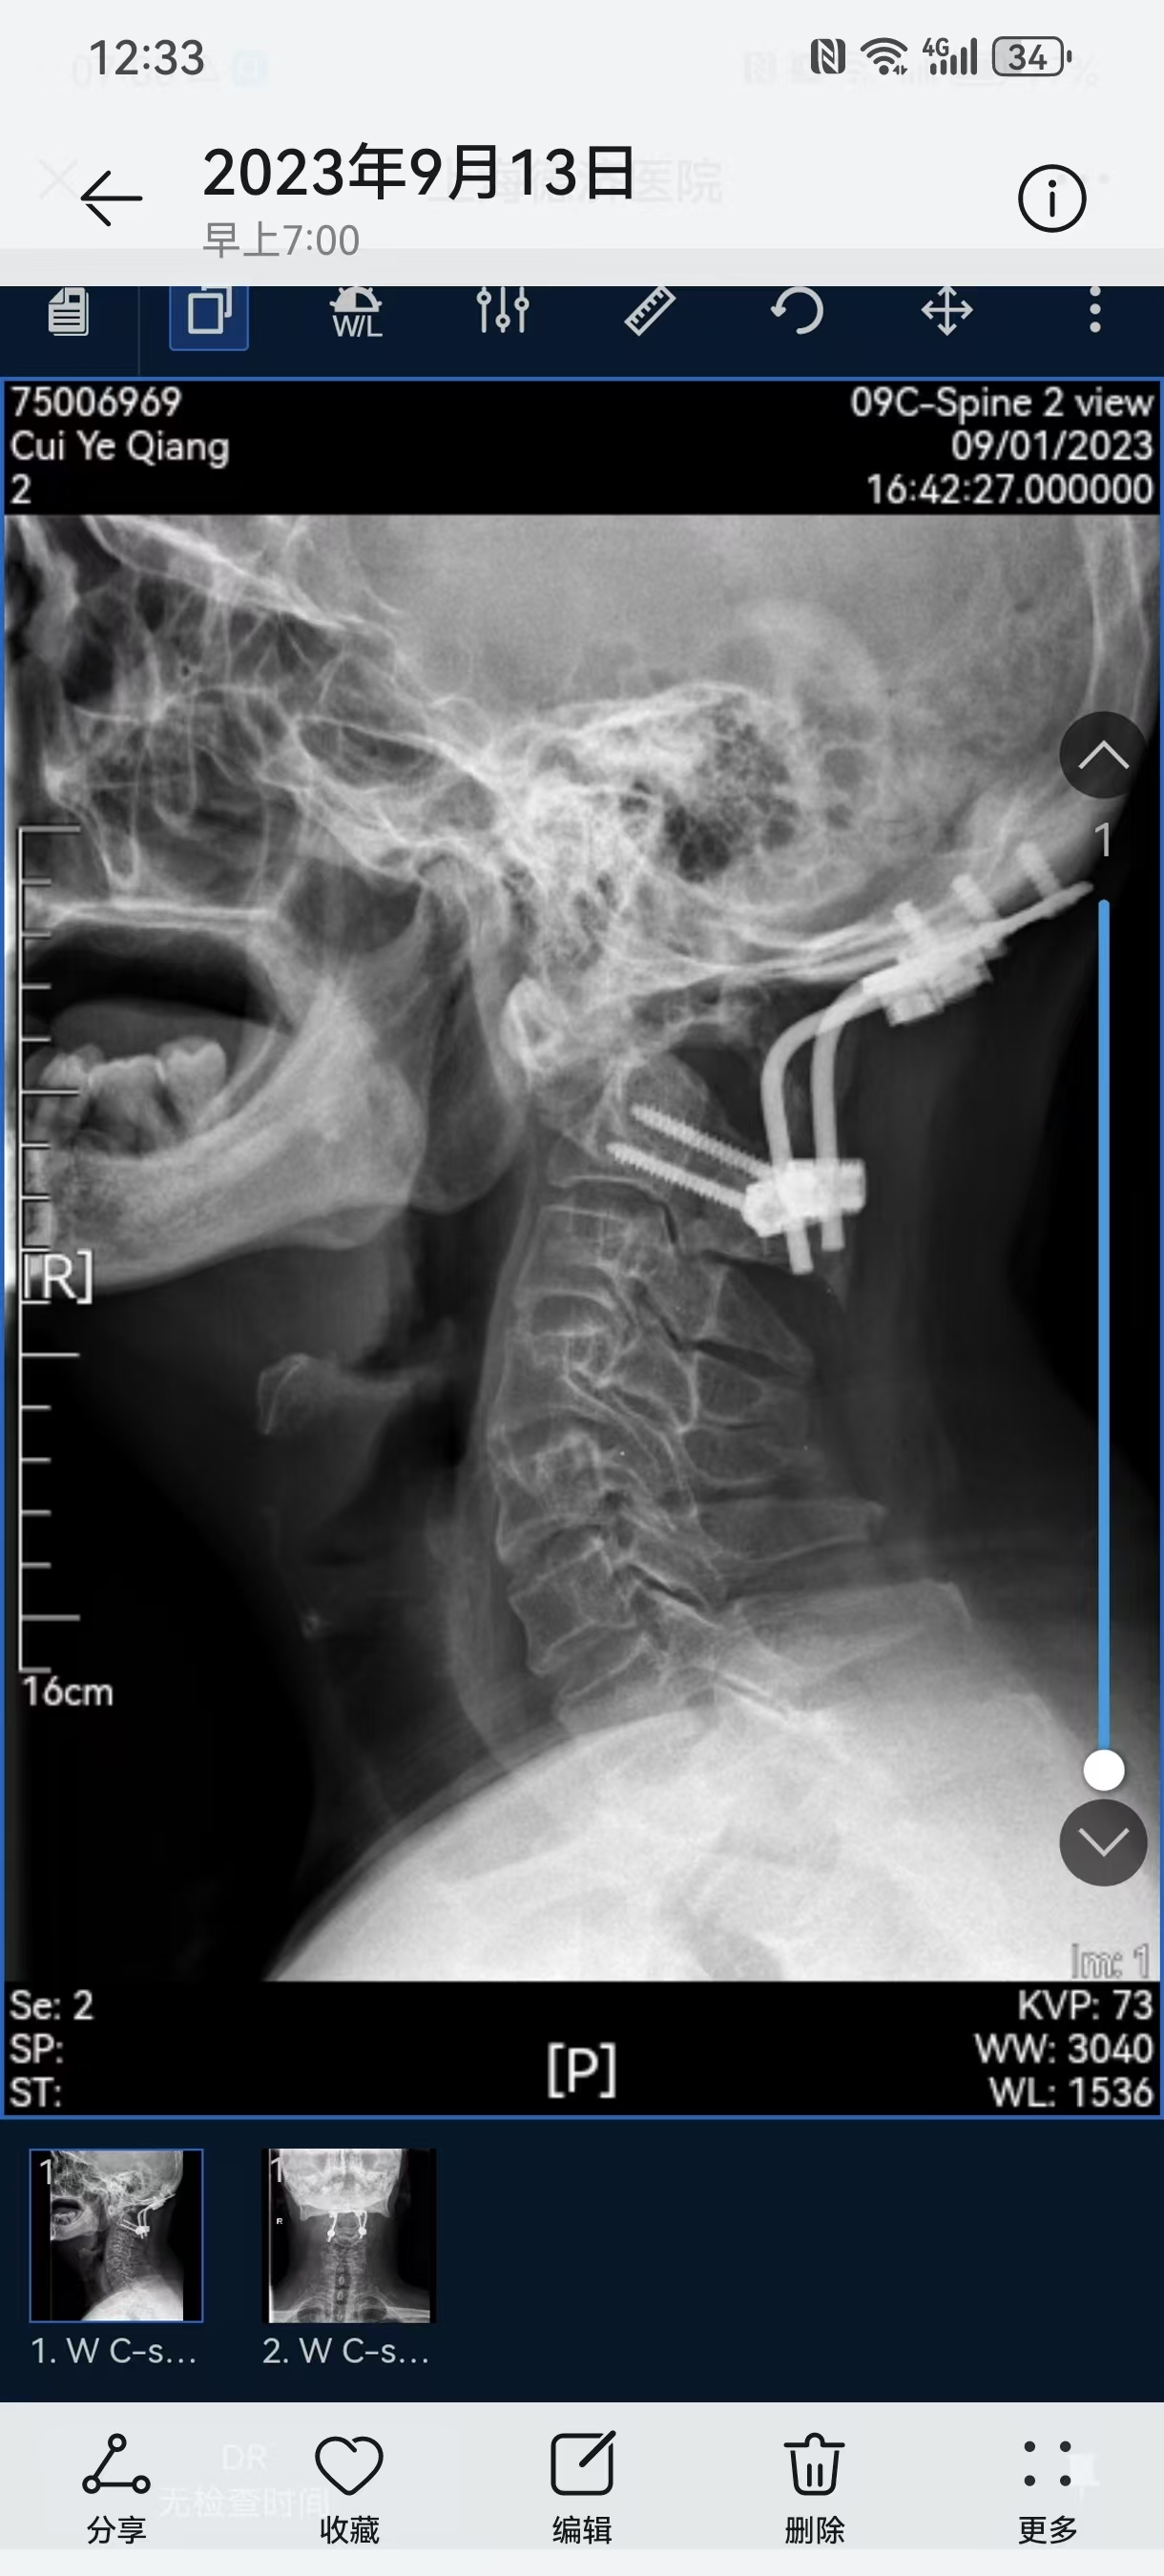

• 诊断:寰枢椎脱位,颅底凹陷

• 2023.09.01,复查,压迫脊髓。